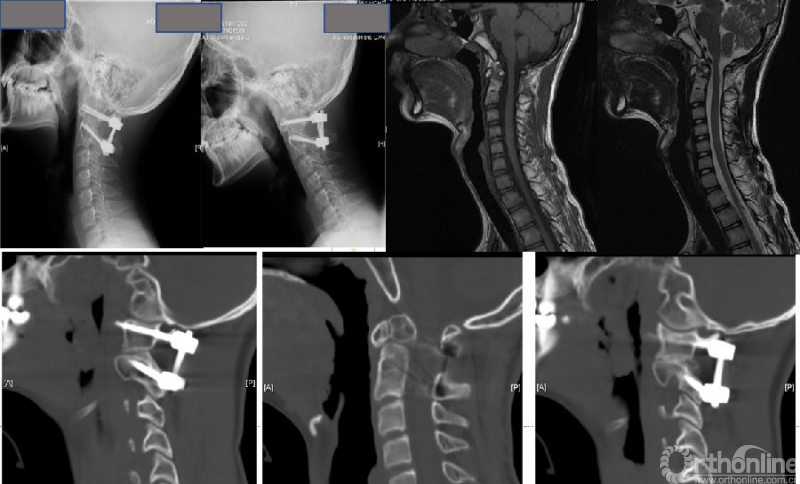

图3:女性56岁;寰枢椎脱位合并寰椎枕骨化畸形、脊髓病。经过动力位X片及术中麻醉后牵引试验,诊断为“难复性寰枢椎脱位”(Type III)。行经口寰枢松解+后路C2椎弓根固定、枕颈固定融合术。寰枢椎脱位获得解剖复位、脊髓压迫解除。